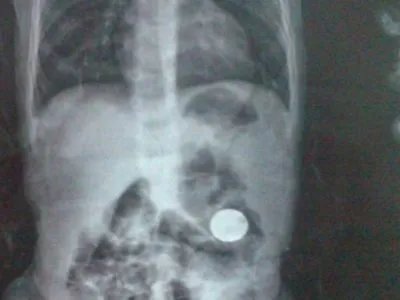

如果硬币到了消化道你而不是进入了呼吸道,如果说进入呼吸道会议及急性窒息的症状,所以说建议去医院拍个腹部平片,查看硬币的所在位置,继续观察大便情况,是有很大几率会随着大便排出的。如果说出现腹痛等症状,要及时的去医院治疗。

患者吃进硬币应迅速前往医院就诊,进行辅助检查,主要拍摄胸部正侧位片和腹部立位平片。还应该观察肠道内有无梗阻的情况,如果确定硬币吞入在胃内应进行急诊胃镜检查,在胃镜检查的同时通过胃镜将其迅速取出,取出后一周内避免食用生冷、辛辣的食物,同时可给予奥美拉唑等药物行胃肠道黏膜的保护。总之应该多注意。